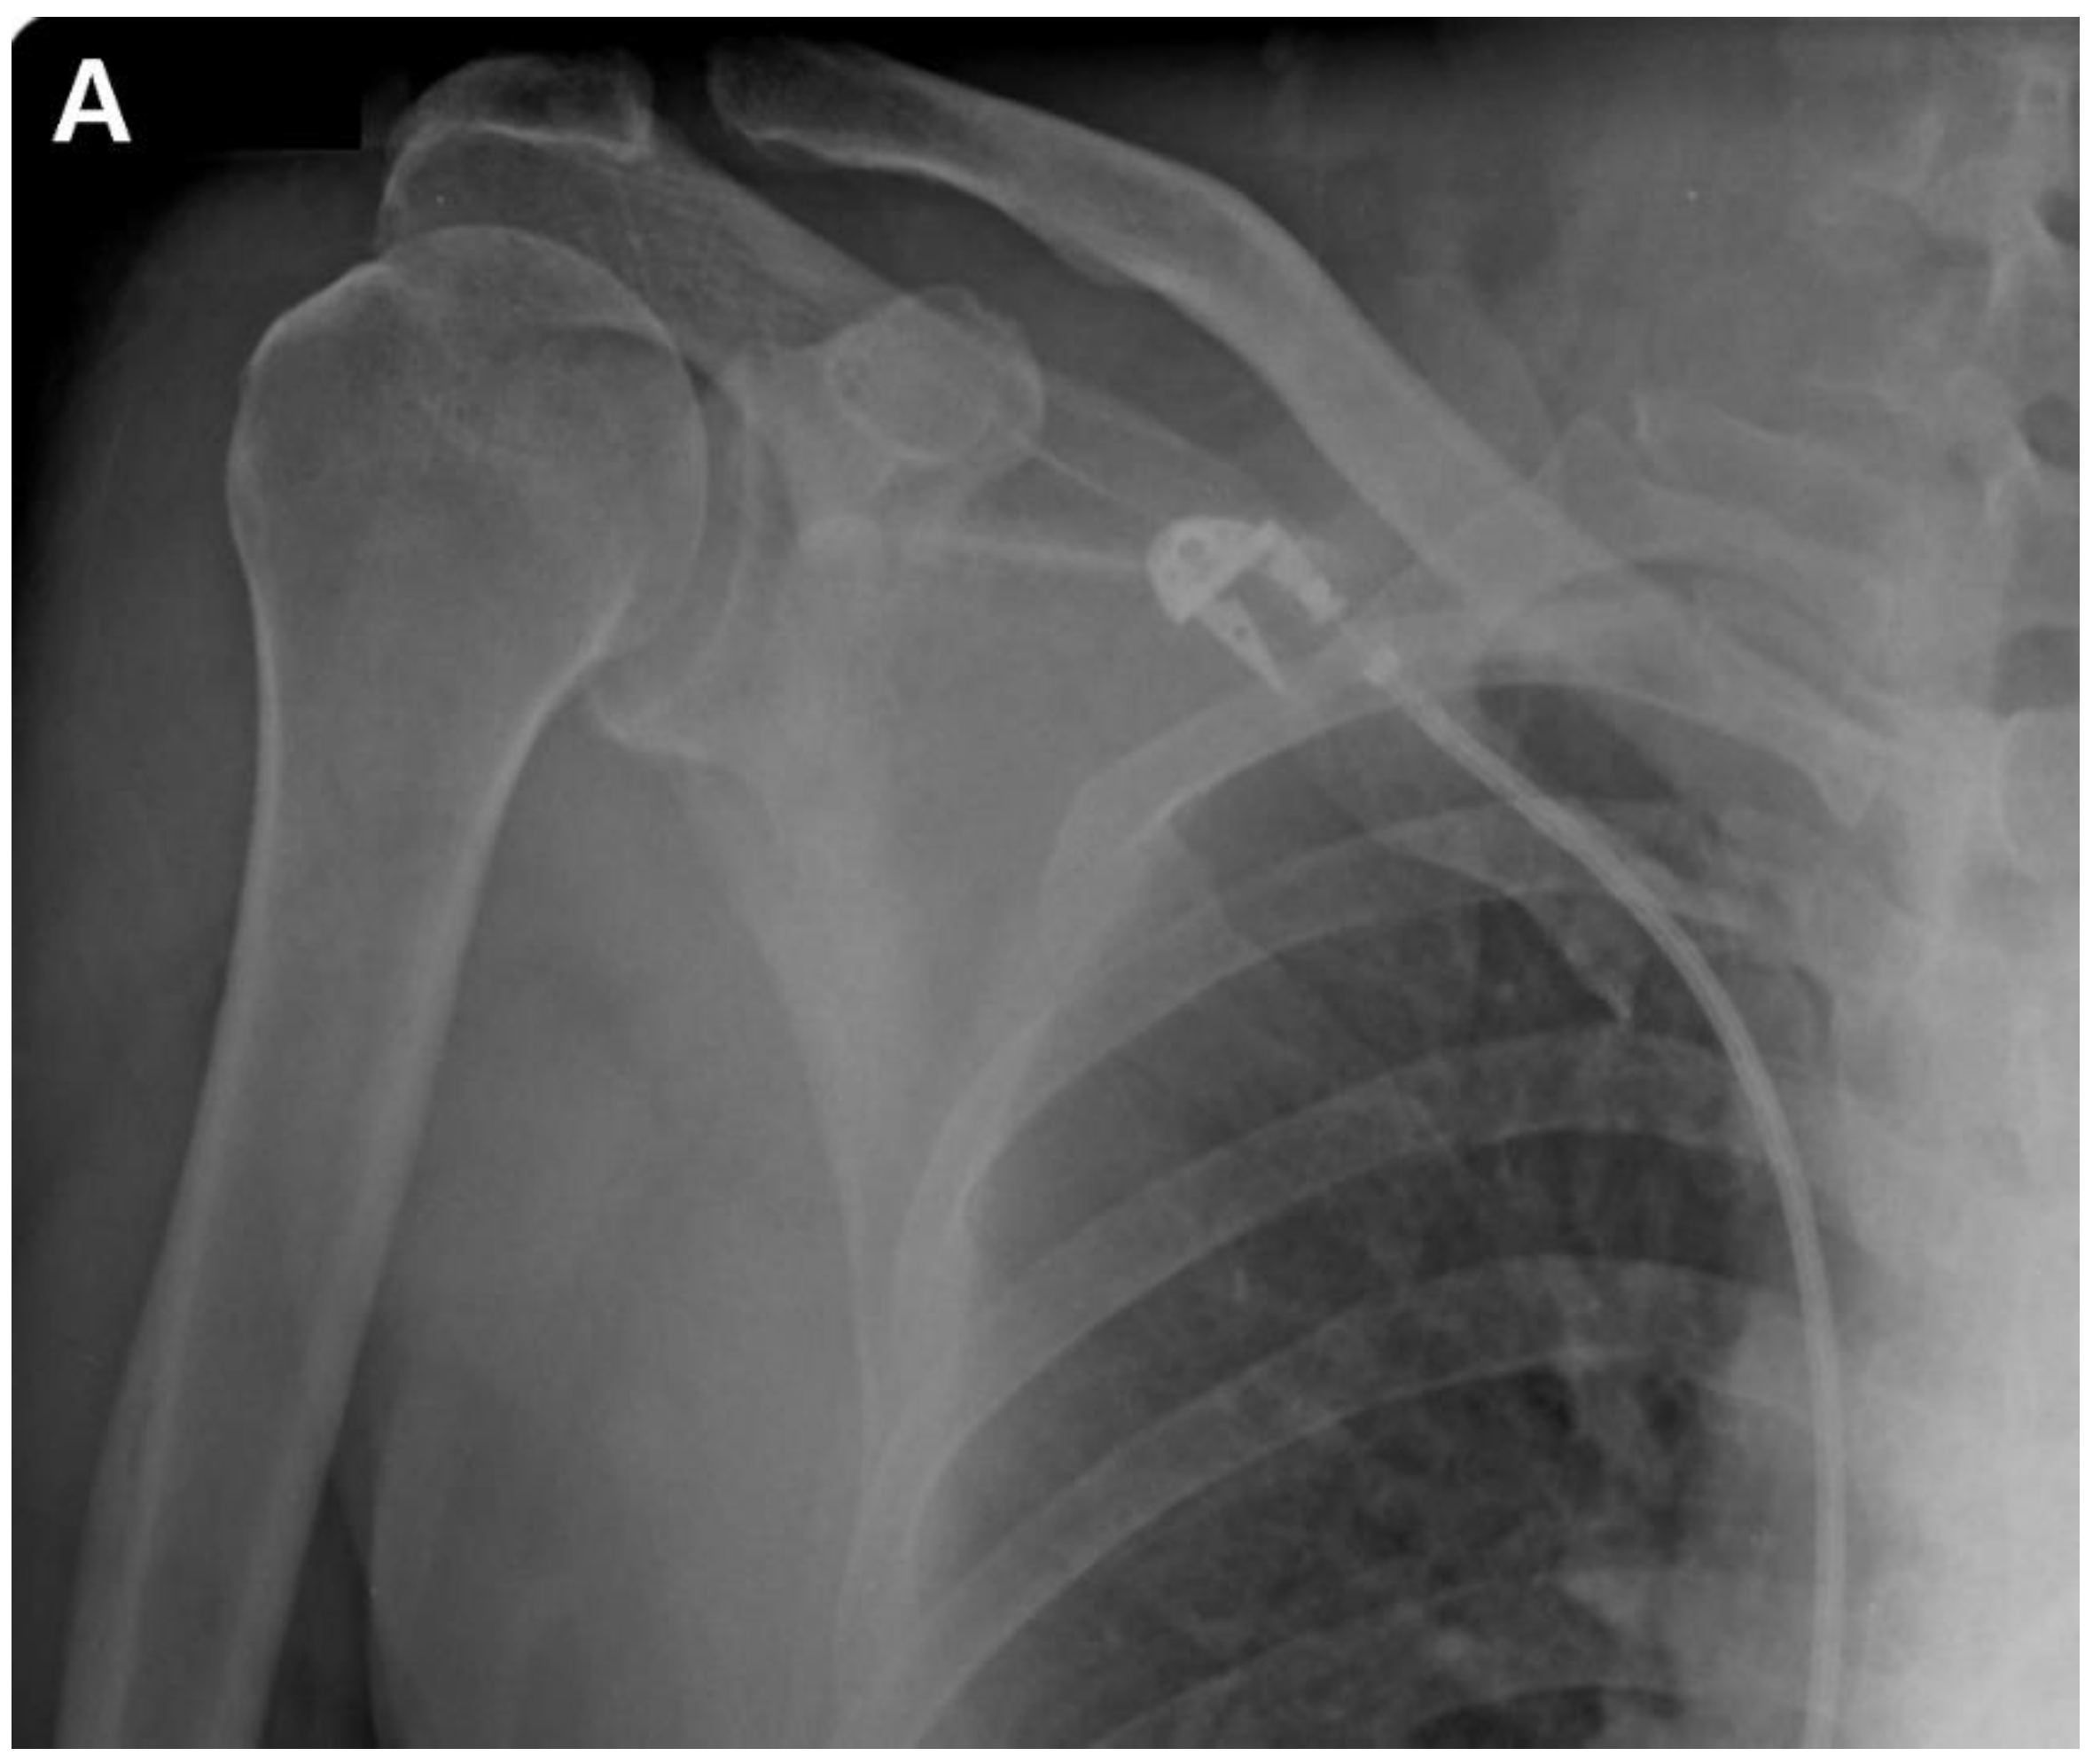

A postoperative scar was observed on the superior aspect along the distal clavicle and acromion, without definite tenderness, swelling, or redness. Preoperatively, the ROM of the affected shoulder was 90° for active forward flexion, 90° for abduction, 40° for external rotation, and sacral level for internal rotation. The visual analog scale (VAS) score was 4, the American Shoulder and Elbow Surgeons (ASES) score was 51, and the Constant-Murley Score (CMS) was 48. Preoperative shoulder radiographs showed acceptable alignment and joint congruency, with no bony spurs or subchondral lesions. Anteroposterior and axillary views of the shoulder radiograph showed acceptable status of acromioclavicular joint reduction without arthritic changes. Magnetic resonance imaging (MRI) showed incomplete signal changes in the supraspinatus muscle, with preserved structural integrity (Fig. 1). Given the patient’s persistent symptoms, which did not improve, the patient had opted for ACR, with informed consent.

Figure 1. A. Preoperative plain anteroposterior radiograph. Acromioclavicular joint alignment was acceptable with no arthritic changes. The glenohumeral joint showed adequate joint space and congruency. B. Oblique coronal T2 fat-suppressed magnetic resonance imaging (MRI). MRI of the right shoulder showed a thickened axillary pouch with normal hypointense joint capsule. The supraspinatus tendon had high signal variation with intact continuity.